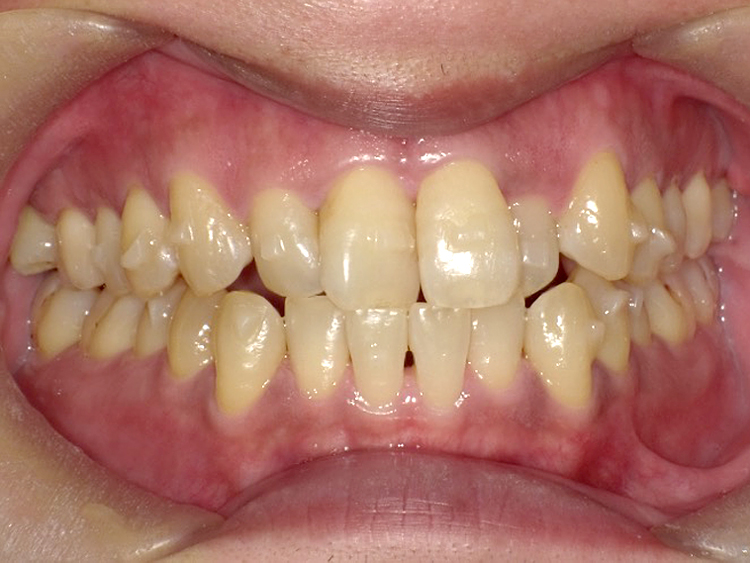

症例3

Before

After

| 主訴 | 上下の歯のガタガタを治したい |

|---|---|

| 年齢 | --- |

| 治療期間 | 約10ヶ月 |

| 治療内容 | インビザラインiGoで上下顎の治療。 狭まっていた歯並びを広げることで、 ガタガタに並んでいた歯を綺麗に並べた。 |

| 治療費 | ¥517,000(税込)+月額調整料 |

| 治療のリスク | 歯と歯の間を削ることでスペースを確保するので、 場合によっては歯が染みる症状が出ることがある。 |